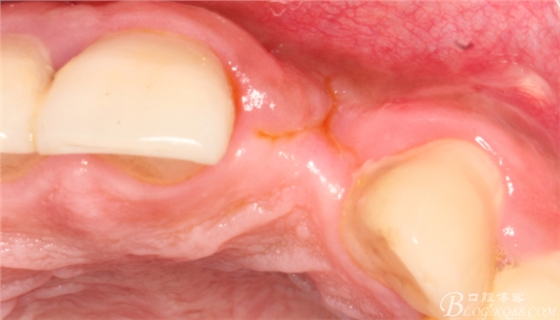

4個(gè)月后,唇側(cè)豐滿度尚可,與鄰牙之間齦乳頭完整。

保留齦乳頭翻小瓣。

翻開后驚喜的發(fā)現(xiàn),術(shù)區(qū)成骨非常好,去除部分骨才暴露那顆長(zhǎng)鈦釘。